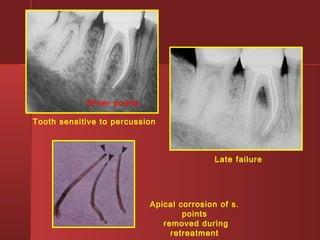

Apical corrosion of s.

points

removed during

retreatment

Tooth sensitive to percussion

Late failure

Apical corrosion ofs. points removed during retreatment Tooth sensitive to percussion Late failure Silver points